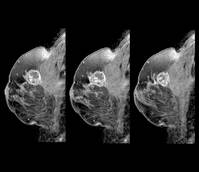

국내 유방암 환자가 꾸준히 증가하는 가운데, 고령 환자 비중이 가파르게 늘어 경각심이 필요하다는 지적이 나오고 있다.◇만성질환을 함께 갖고 있는 경우 많은 고령 환자국민건강보험공단 자료에 따르면 국내에서는 매년 3만5000명의 유방암 환자가 새롭게 발생하고 있는데​ 지난 2021년 기준 50~60대의 환자가 전체 60.8%를 차지했다. 무엇보다 신규 암환자의 경우 절반 이상이 65세 이상 환자였다. 국가암통계 자료에 따르면 2023년 신규 암환자의 경우 65세 이상 환자가 50.4%를 차지했다.전문가들은 고령 유방암 환자 증가의 주요 원인으로 인구 고령화와 서구화된 생활습관을 꼽는다. 우리나라는 빠른 속도로 고령사회에 진입하고 있으며, 평균수명 증가에 따라 암 발생 위험이 높은 고령 인구 자체가 크게 늘고 있다.여기에 식습관 변화와 비만, 운동 부족, 늦은 출산 및 적은 출산 경험 등 서구화된 생활양식도 유방암 증가에 영향을 미치는 것으로 분석된다. 실제 국내 유방암 발생 양상도 과거 젊은 연령층 중심에서 점차 서구 국가처럼 고령층 비중이 커지는 방향으로 변화하고 있다.가천대 길병원 외과 김윤영 교수는 “과거에는 비교적 젊은 여성의 질환으로 여겨졌던 유방암이 이제는 고령층에서도 흔하게 발생하고 있다”며 “고령 환자는 다른 만성질환을 함께 갖고 있는 경우가 많아 조기 발견과 적절한 치료 시기 결정이 더욱 중요하다”고 말했다.◇40세 넘었다면 주기적으로 유방촬영술 권고다행히 유방암은 조기에 발견할 경우 치료 성적이 매우 좋은 암으로 꼽힌다. 초기 단계에서 발견하면 장기 생존율이 높고, 치료 후 일상 복귀도 비교적 빠르다. 반면 진행된 이후 발견되면 치료가 복잡해지고 예후도 나빠질 수 있다.유방암의 발생에는 가족력, 비만, 음주, 운동 부족 등이 대표적인 위험 요인으로 알려져 있다. 특히 폐경 이후에는 체중 관리가 중요하다. 규칙적인 운동은 유방암 발생 위험을 약 10~20% 낮추는 것으로 알려져 있으며, 빠르게 걷기 같은 유산소 운동을 주 4~5회, 한 번에 20~30분 정도 시행하는 것이 도움이 된다.또 유방암은 초기에는 통증이 없는 경우가 많아 증상이 없더라도 정기적인 검진이 중요하다. 일반적으로 40세 이후에는 1~2년에 한 번 유방촬영술 검진이 권고된다. 평소 멍울이나 피부 함몰, 유두 분비물 같은 변화를 확인하는 자가검진 습관도 도움이 된다.특히 치밀유방이 많은 국내 여성에서는 초음파 검사가 중요한 역할을 한다. 이후 필요 시 조직검사를 통해 정확한 진단을 내리게 되며, MRI 검사를 통해 병변의 범위를 추가적으로 평가하기도 한다.김 교수는 “특히 고령층에서는 ‘나이가 들어서 그렇다’며 증상을 방치하거나 검진을 미루는 경우가 많다”며 “조기에 발견하면 충분히 좋은 치료 결과를 기대할 수 있는 만큼 정기 검진을 미루지 않는 것이 중요하다”고 말했다.